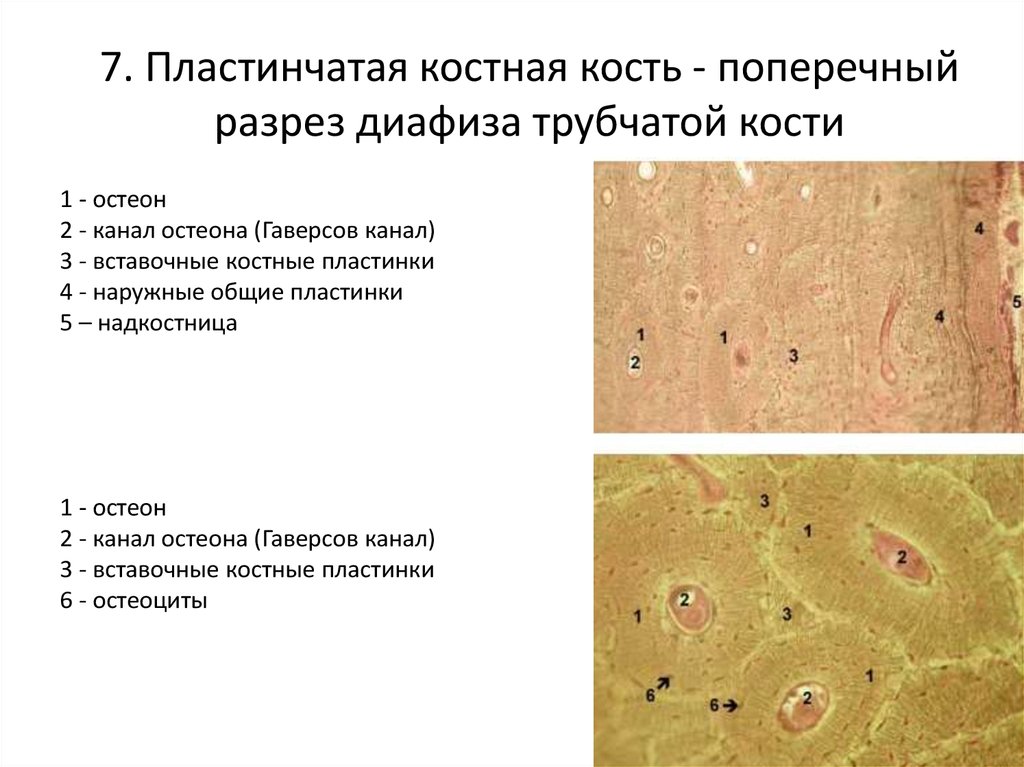

Структура грубоволокнистой костной ткани: наглядные примеры